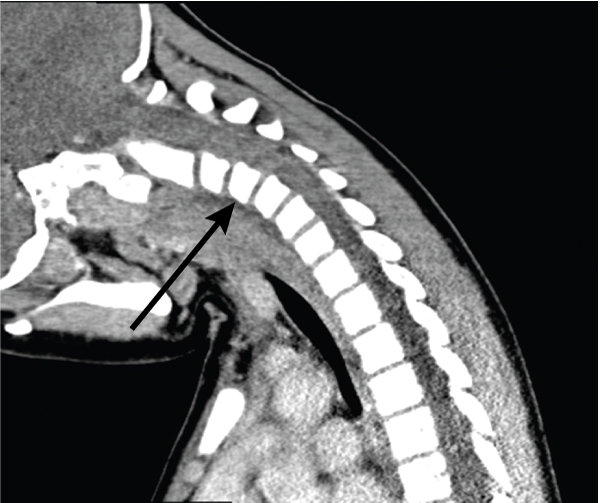

On Day 11, in view of ongoing neck pain and torticollis, a computed tomography (CT) scan of the patient’s neck showed rotational atlantoaxial subluxation, with C1 rotated to the right relative to C2, and persistent bilateral cervical lymphadenopathy (Box 1 and Box 2). The other feature on the CT scan was a hypodense region in the retropharyngeal area measuring 6 mm anteroposteriorly and 7.6 mm mediolaterally, possibly indicating a retropharyngeal abscess (Box 3). Intravenous cefotaxime and lincomycin were therefore continued for 14 days. The patient was placed in cervical traction for 8 days to reduce the subluxation, followed by visor orthosis (a rigid vest and collar) to immobilise her neck.

The pathophysiology of the association between KD and retropharyngeal abnormality is unclear. CT scans of the neck in the previously reported cases and in our patient revealed hypodense lesions suggestive of a retropharyngeal abscess. While CT has 90% sensitivity for detecting deep neck lesions, some studies showing only 60% specificity for differentiating between inflammation and infection have cast doubt on whether CT scans can identify the cause of the lesion.7 It has been suggested that once a patient is diagnosed with KD, the abscess-like lesion on the CT scan should be viewed as a type of inflammation rather than infection.8 In our patient, magnetic resonance imaging may have been superior for differentiating between inflammation and infection but would probably have been inferior for assessing for subluxation and would have been technically difficult because of traction equipment.